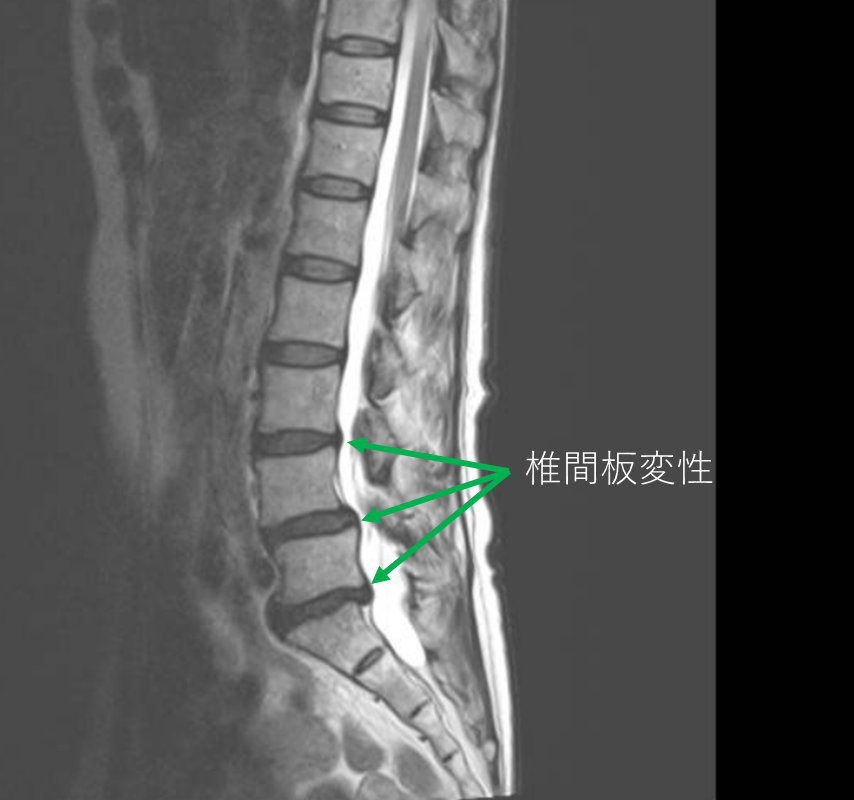

画像及び所見について

- L3/4,4/5,5/s-椎間板変性

- L5-後方滑り

以上の事が画像上認められます。

・L3/4,4/5,5/s-椎間板変性を認め、主症状の原因の可能性が高い。